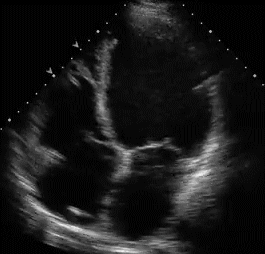

Still unclear ? Look for the wall motion defects in echo . An echo cardiogram (Need to be meticulous ) will help match the dysfunctional segment with IRA.

Wall motion defects are notoriously error prone in ACS for two reasons.

- We do not have easy and accurate methods to differentiate ischemic wall motion defect from infarct related wall motion defects.

- Tethering artifacts , differential behavior epicardial vs endocardial ischema on contractility will confound the issue .